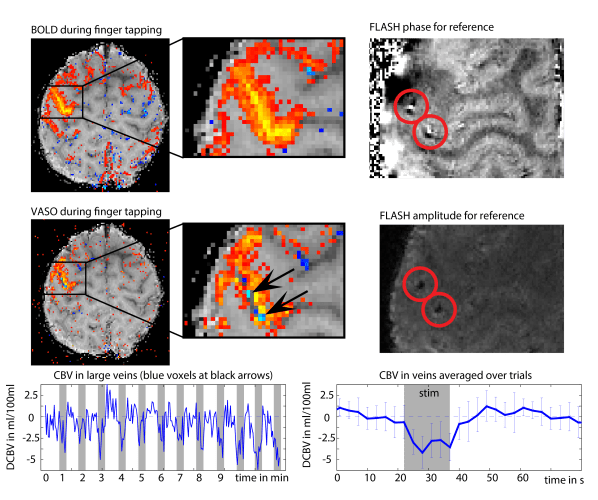

2.) Venous constriction

The skull can be considered as a container with a fixed volume and cannot be expanded. As soon as one compartment increases its volume, another compartment needs to reduce its volume accordingly. Until now its it still not really established how this mechanism works and how the substantial CBV increase during increased brain activity is accounted for. Dependent on the task duration, activation region size, and activation strengths, CBV increase seems to be jointly compensated by GM-volume decrease, CSF-volume decrease and decrease of venous blood volume.

The last option, the decrease of venous blood volume, can thus also be one possible reason for negative VASO signal change and has been described here.

In my experience, this effect is more common than inflow effects and it is mostly happening in the upper layers and above the cortex.

I found that these voxels are most easily identified by mapping the correlation of the VASO and the BOLD fluctuation. E.g. with the LAYNII program LN_CORREL2FILES.